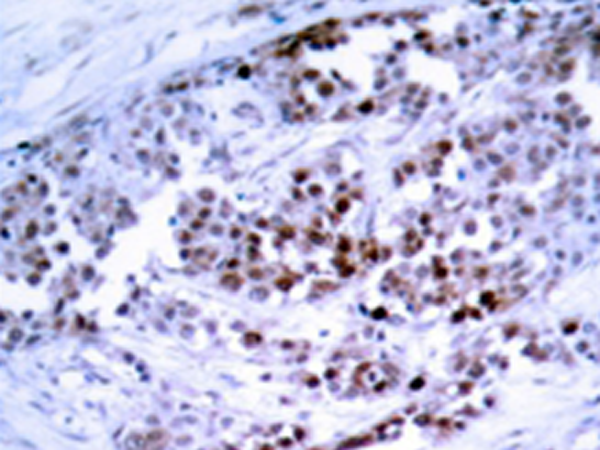

IHC |

IHC positive control: |

Human breast carcinoma tissue |

IHC Recommend dilution: |

50-100 |